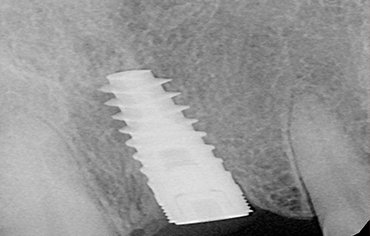

After clinical examination and radiographic assessment[ CBCT, OPG], a small opening is made in the gums to expose the bone. Surgical guides are prepared and implant made up of TITANIUM is placed. Once the IMPLANT is placed, bone is deposited and the implant unites with the bone. After placing the implant perfectly, ABUTMENT is placed . Abutment is a post that connects implant to the prostetic tooth. After 2-3 weeks artificial tooth is placed.